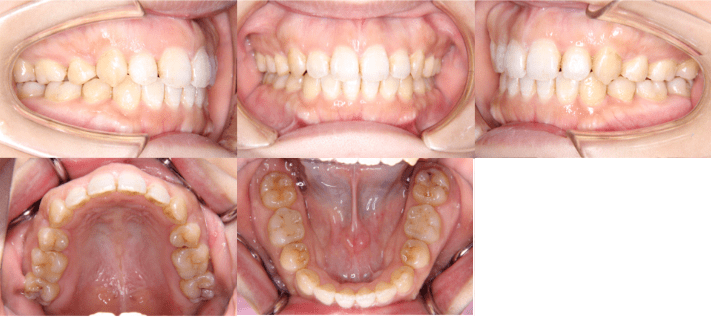

治療前

• 初診時年齢:28歳4ヶ月

• 主訴:前歯のかみ合わせ

• 診断:開咬

• 治療内容:小臼歯4本を抜歯した後に、マウスピース型カスタムメイド矯正歯科装置(製品名インビザライン 完成物薬機法対象外)を使用して主訴である開咬の改善を行いました。

• 治療期間:2年

• リスク:矯正治療による歯の移動に伴う痛み、歯根吸収、虫歯

• 費用:80万円